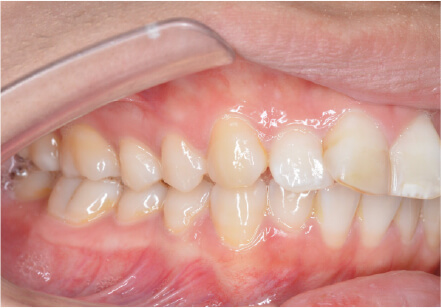

叢生の症例

10歳

/

女性

相談内容

スペース不足

カウンセリング・診断結果

myoからの移行。スペース不足のためインビザライン開始。

治療内容・方法

全額アライナー矯正

術後の経過・現在の様子

クリアライナー使用

治療のリスク

痛み・歯根吸収・歯肉退縮・虫歯・後戻り

費用・治療期間

(インビザのみ)385,000円、1年2ヶ月 + myo3年4ヶ月

トレーニングなど